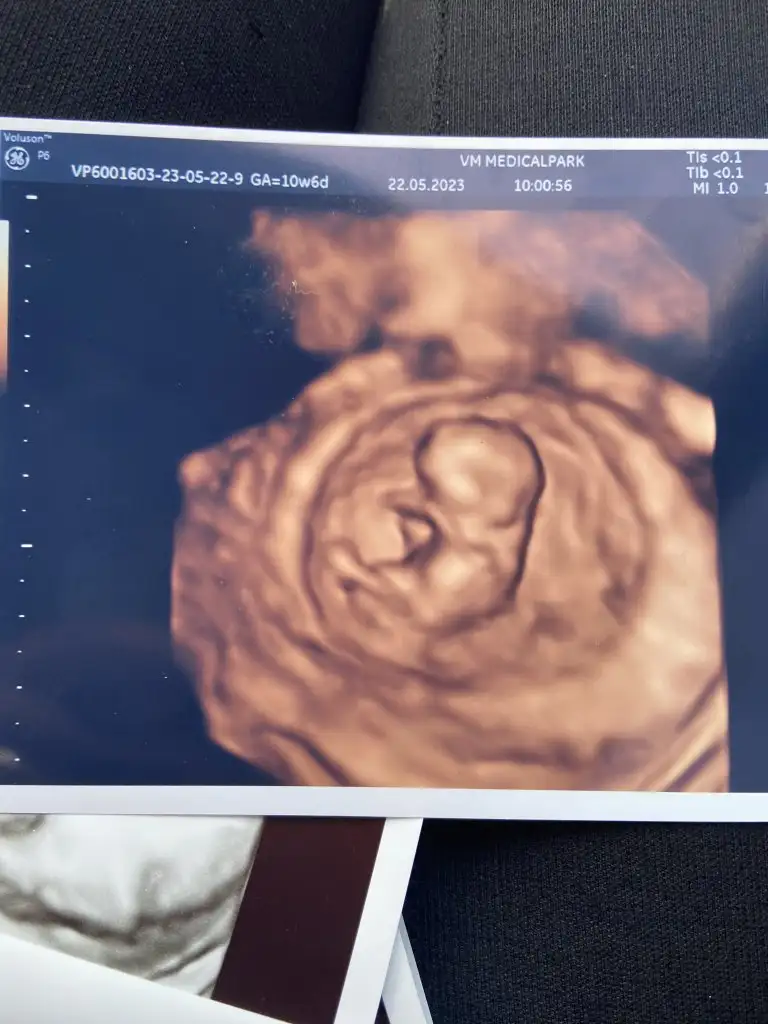

Bebek şükür iyi.

9+4 olmuş.